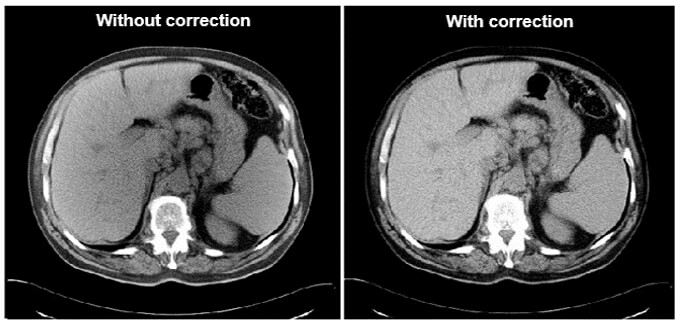

Metal implants such as shrapnel, surgical clips, pacers, joint prostheses, wires, pedicle screw placement, stenting, usually undergo follow-up CT imaging. These metallic implants lead to severe streak and shadow artifacts in CT images that superimpose the structures of interest and deteriorate image quality. This is because metallic objects are a high-density material, which is strongly scattered to the transmitted x-ray beam during CT examination.

Various metal artifact reduction techniques have been developed to reduce metal artifacts, and the most commonly used reconstruction algorithm for CT has filtered back projection (FBP), interpolation methods, and iterative reconstruction methods.

Streaking caused by over ranging can be greatly reduced using special software corrections. Manufacturers use a variety of interpolation techniques designed to substitute the over ranged values in attenuations’ profile.

However, there is always a detail loss around the metal/tissue interface, which is often the area of interest in diagnosis.

This image shows the effectiveness of metal reduction artifact software. Notice how much better the resolution is in the image on the right.